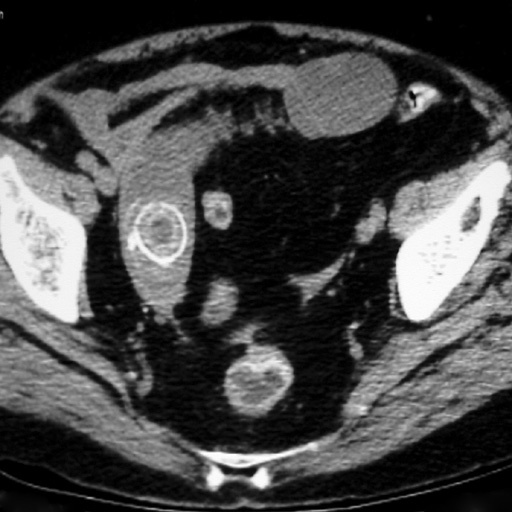

Le patient a une diverticulite. Devant persitance fièvre et augmentation du sd inflammatoire à 48h on réalise le TDM suivant. Vu la taille de l’abcès (>5 cm on va dire), quelle CAT?

drainage de l’abcès: ponction percutanée écho ou scanno-guidée; OU drainage chirurgical si percut impossible (avec RDC à distance)